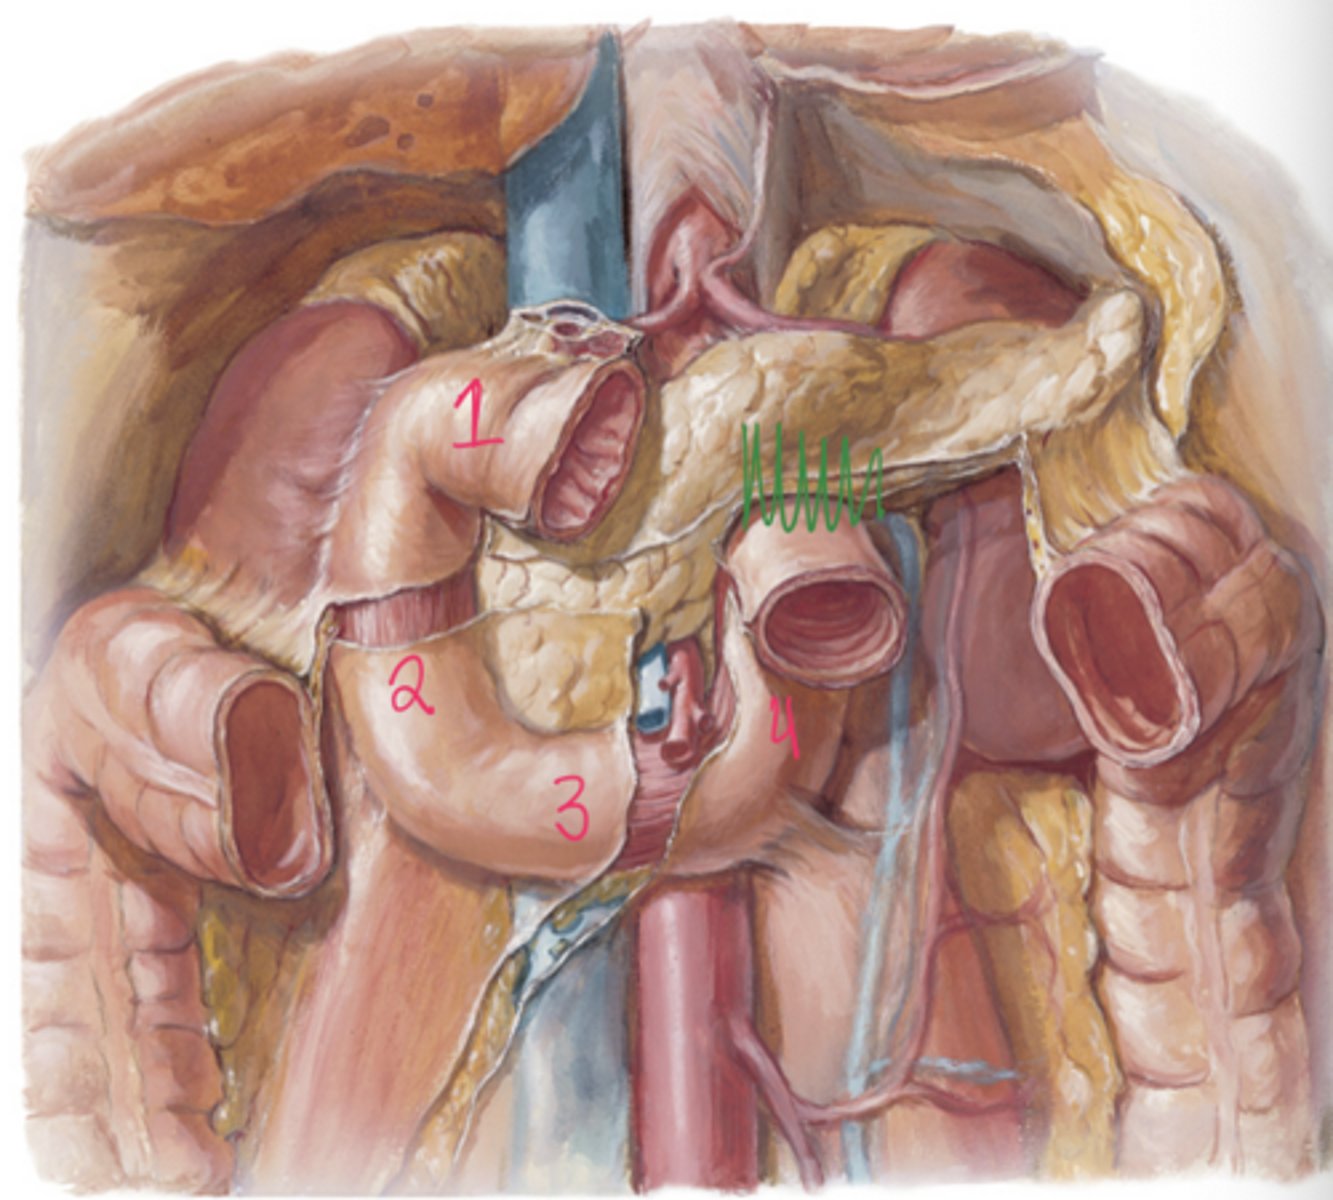

What are the four parts of the duodenum?

Superior (1st), descending (2nd), inferior (3rd), and ascending (4th) portions.

Where do the pancreatic and bile ducts enter the duodenum?

They enter the second (descending) part of the duodenum at the major duodenal papilla

What is the accessory pancreatic duct?

smaller duct that empties directly into duodenum via minor duodenal papillae (NOTICE this is ONLY pancreatic juices NOT BILE)

1. R hepatic duct

2. L hepatic duct

3. Common hepatic duct

4. Gallbladder

5. Cystic duct

6. Common bile duct

7. Pancreatic duct (major)

Endoscope also seen

Label the radiograph